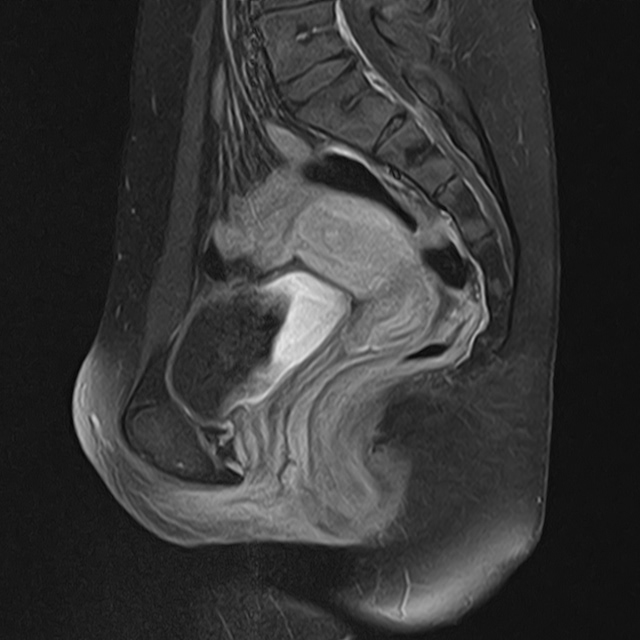

Una narrazione visiva del mio percorso fino alla diagnosi di Adenomiosi e Vulvodinia.

Nascosta in Piena Vista è un progetto fotografico che nasce dall’esigenza di provare a descrivere visivamente un’esperienza soggettiva come quella del dolore.